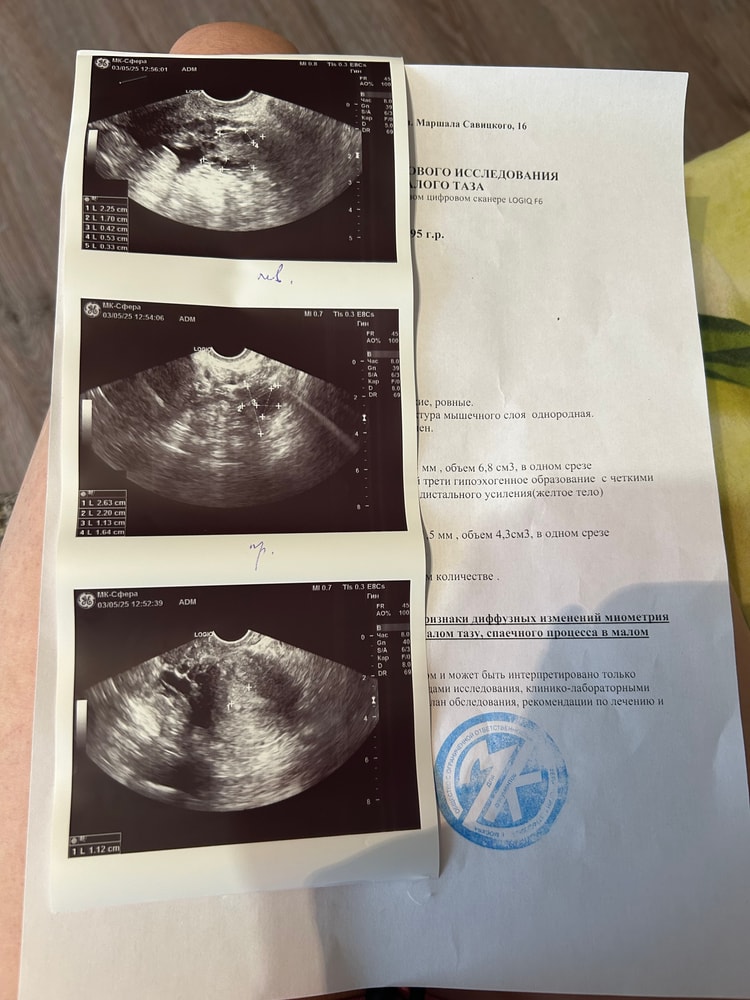

Алина в Зачатие 7 месяцев Сходила на узи на 51 дц УЗИ Всем привет ,сказали жидкость позади матки и вокруг левого яичника ,Нужна консультация гинеколога,но овуляция была ,но где же месячные 🩸 может она была недавно Посмотрите еще 20 записей на эту тему Отменить Ответить ДФ 21 мм, через сколько может лопнуть? Дф 12 мм Чаты Беременных Выберите чат: Январята-2026 Февралята-2026 Мартята-2026 Апрелята-2026 Майчата-2026 Июнята-2026 Июлята-2026 Августята-2026